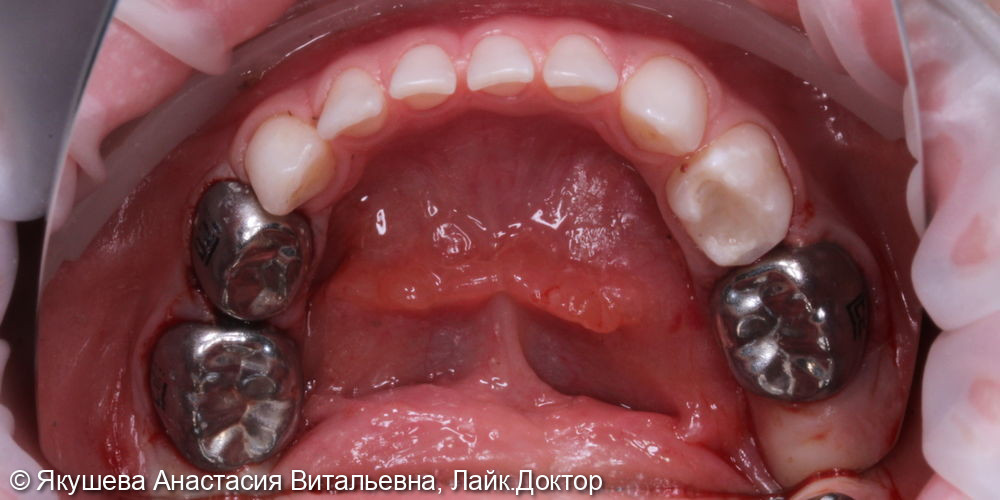

55;54;64;85;84;74;75 : К04.0 Пульпит (K04.0 Пульпит)

55;54;64;85;84;74;75 : в условиях общего обезболивания: очищение мягкого зубного налета, изоляция коффердам, проведено препарирование кариозной полости, раскрытие полости зуба, проведена пульпотомия, достигнут гемостаз,Показать полностью...

55;53;65;74 : в условиях общего обезболивания очищение мягкого зубного налета, изоляция коффердам, проведено препарирование кариозной (ых) полости (ей), под контролем витального окрашивания «Кариес Маркер» удалены деминерализованные участки эмали и дентина, формирование кариозной полости антисептическая обработка раствором хлоргексидина 2%,Показать полностью...